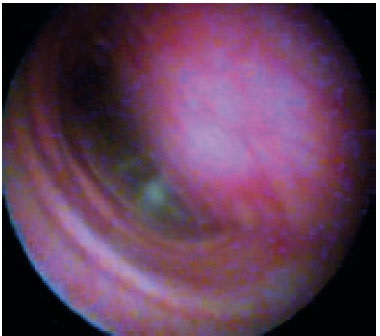

Diagnózis lehet eredményeként X-sugarak a betegek az oldalsó fekvő helyzetben. Fluoroszkópiát jobb a diagnosztikus értékű, mint a röntgenfelvételek, mivel Ez lehetővé teszi láthatóvá a légcső mozgásban alatt lélegzik. Ha ez nem lehetséges, hogy végezzen röntgen, szükség van a kellően pontosan megragadni a pillanatot belélegzés vagy kilégzés a röntgenfelvételen. X-sugarak a cervicalis trachea osztályának hajtja végre, amikor az inhalációs, mellkasi tracheális osztály - idején lejárati. A nehéz betegek röntgen végezhető álló oldalsó pozícióban (ris.1,2).

Endoszkópia a legjobb diagnosztikai értékeléséhez a légcső és a hörgők, de végrehajtására csak érzéstelenítéssel. Bronchoszkópia lehetővé teszi, hogy belsejében a légcső az egész hosszában, hogy értékelje az állam az nyálkahártya, hogy értékelje a mozgás a légcső során légzési ciklust. Tracheoscopy „arany standard” diagnózis és használják megerősíteni a diagnózist. A jelenléte a változások a lumen a légcső és a hörgők 4 fok trachea összeomlása. A légcsövet a „normális” van egy csaknem kör alakú annak teljes hossza mentén. Az egészséges állatok légcső áll sobraznyh alakú porcos gyűrűk egymáshoz háti légcső membrán. Dorsalis tracheális membrán általában tekinteni, mint a hosszanti simaizom rossz szakaszok során lélegzik. A légcsövet borított nyálkahártya, amelyeket át nézve a porcos gyűrűk. Nyálkahártya „OK” úgy néz ki, sima, halvány rózsaszín, nyálkahártya alatti réteg gazdag áthatja kapillárisok (3. ábra). Ha a szint 1 tracheális összeomlása is megfigyelhető, hogy az alak a légcső alig változott, dorzális membrán enyhén laza, a porc gyűrűk alátámasztó normális formában légcső, a légcső lumen csökken mintegy 25% (4. ábra). Amikor a 2. fokú összeomlás dorzális membrán kifeszített és laza, kissé lapított porcos gyűrűk, tracheális lumen 50% -kal csökken (5. ábra). Összecsukása 3. fokozatú azzal jellemezve, hogy a dorzális membrán laza úgy, hogy szinte érinti a dorzális a porc gyűrűk porcos gyűrűk dorsoventrally lapított, tracheális lumen csökken 75% (6. ábra). 4. fokú összeomlása a légcső: dorzális membrán fekszik a porcos gyűrűk légcsőgyűrűket lapított és telepített gyakorlatilag nem légcső lumen (7. ábra) (a Tangner CH, Hobson HP: Egy retrospektív vizsgálatban 20 kezelt esetek összeesett légcső / Vet Surg 11: 146, 1982).